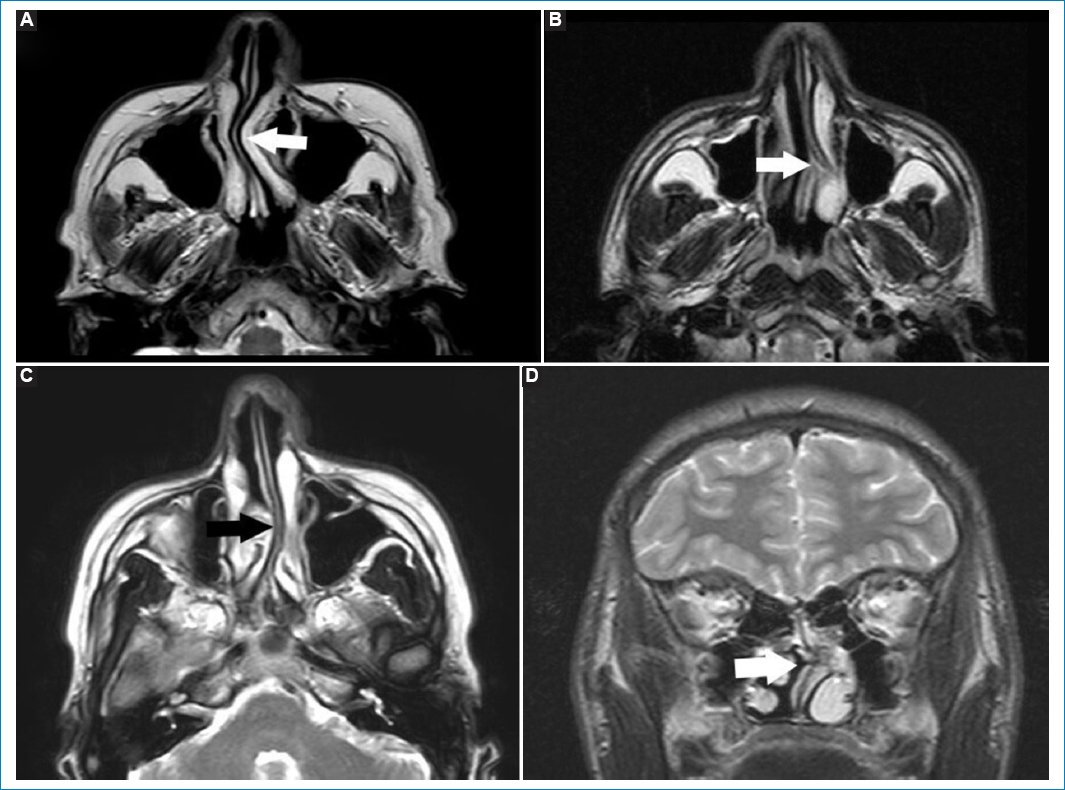

Se observan como elevaciones convexas hacia la luz de un seno paranasal, hipointensos en T1 e hiperintensos en T2 (Fig. 1)10.

Figura 1. Quiste de retención. Secuencias potenciadas en T2, cortes axiales (A-C) y coronal (D). Las flechas rellenas señalan a los QR, caracterizados como imágenes ovoideas de bordes bien delimitados, hiperintensas en T2, por su contenido líquido.

La desviación del tabique nasal puede ser congénita o producirse por un trauma, y tiene una prevalencia mayor al 76%14; se produce cuando el tabique (septo) se aleja de la línea media y se aproxima a los cornetes14. Puede ser asintomática u ocasionar rinosinusitis, ronquido o apnea del sueño14.

La TC es el método de elección para estudiar la desviación septal15. La RM permite una mejor valoración de los tejidos blandos (Fig. 2)16.

Figura 2. Imágenes potenciadas en T2. Cortes axiales (A-C) y coronal (D). Las flechas rellenas señalan las diferentes desviaciones del septo nasal, obliterando parcialmente la vía aérea.

La hipertrofia adenoidea puede observarse en pacientes jóvenes o en adultos jóvenes, atópicos o roncadores. Es evidenciable en RM como una masa de tejidos blandos, con estrías y quistes de retención pequeños; es hiperintensa en T2 e isointensa e T1, disminuyendo la vía aérea parcialmente (Fig. 3)17.

Figura 3. (A y B) Cortes axiales ponderados en T2. Las flechas señalan la hipertrofia adenoidea en dos pacientes distintos. Se aprecia engrosamiento hiperintenso con microquistes asociados, obliterando parcialmente la luz de la vía aérea.

Podemos definir al meningocele como una herniación de la duramadre, formando una colección anormal de líquido cefalorraquídeo (LCR), que comunica con el espacio de LCR que rodea al cerebro o la médula espinal18.

Tienen una incidencia de 1-3 cada 10.000 niños, y pueden tener origen congénito, traumático o atraumático19.

La RM permite valorarlos como hiperintensos en T2 e hipointensos en T1, dado su contenido de LCR (Fig. 4)20.